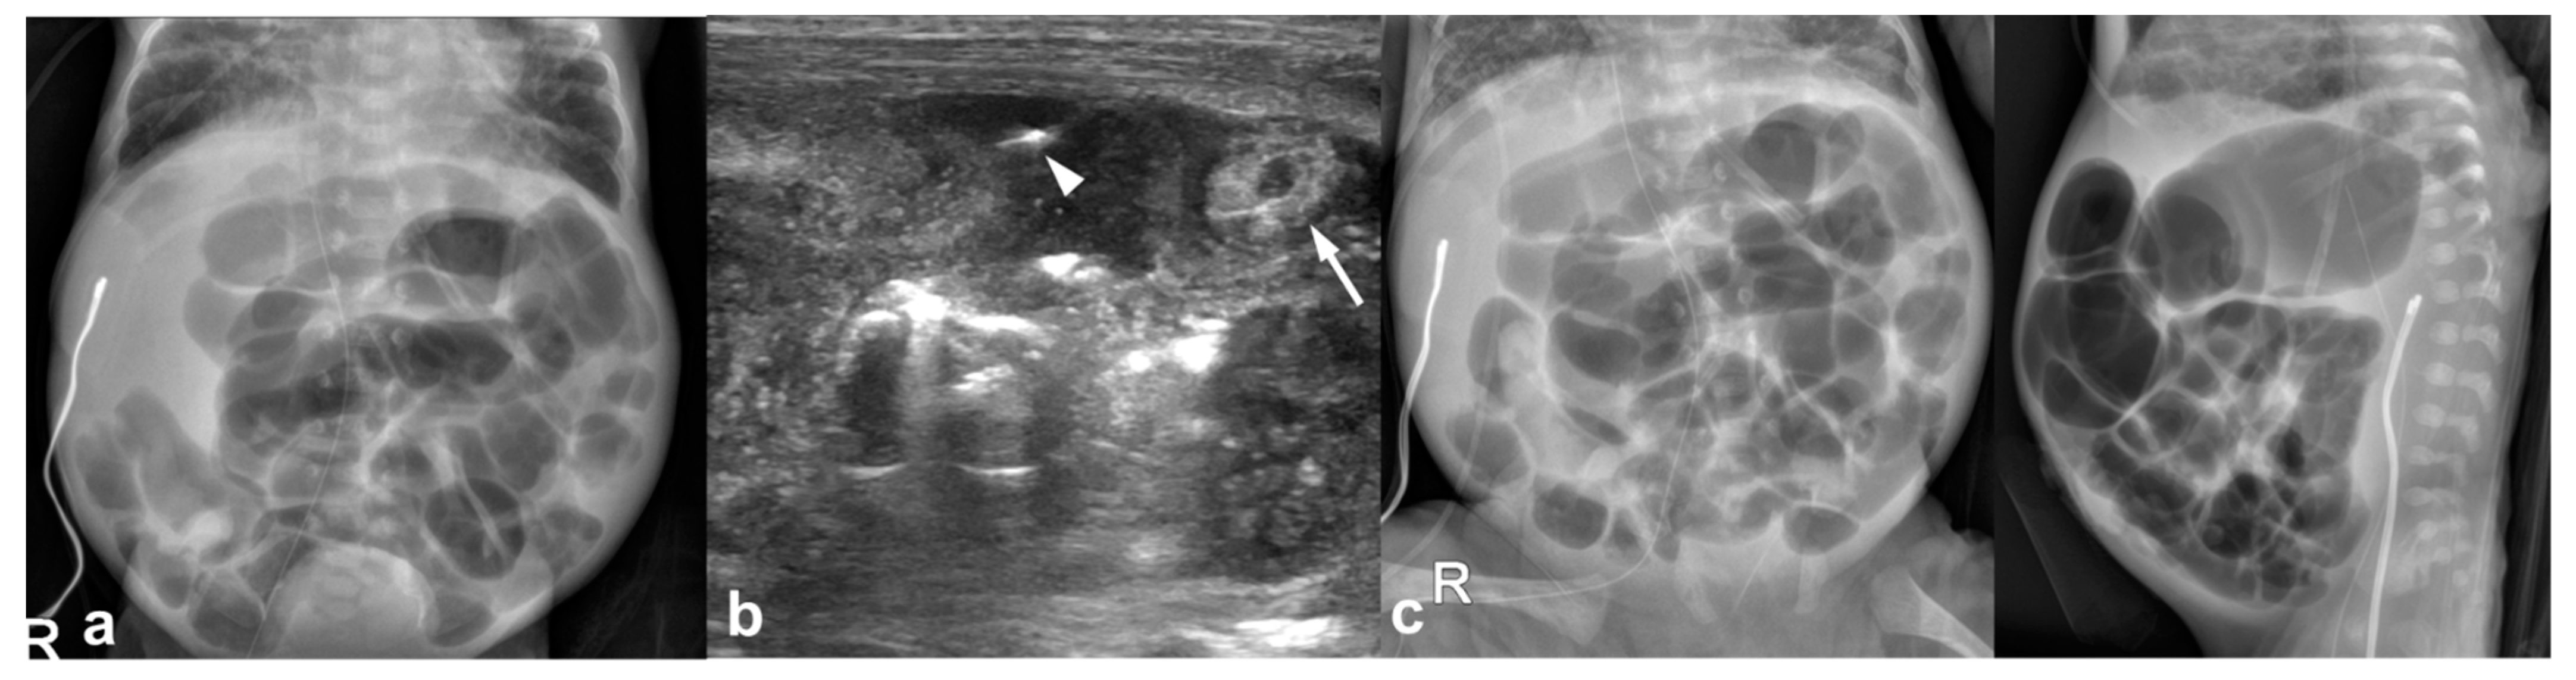

Figure 1.

22-day-old girl (born at gestational age of 25 weeks and 3 days) with US-detected perforated necrotizing enterocolitis without radiographic pneumoperitoneum; this infant survived. (a) An abdominal radiograph obtained 7 h before US shows ileus with elongated loops and no pneumoperitoneum. (b) Preoperative US images show bowel wall thickening (arrow) and free air within the complicated ascites (arrowhead). (c) Preoperative abdominal radiographs obtained 30 min after US show no pneumoperitoneum.